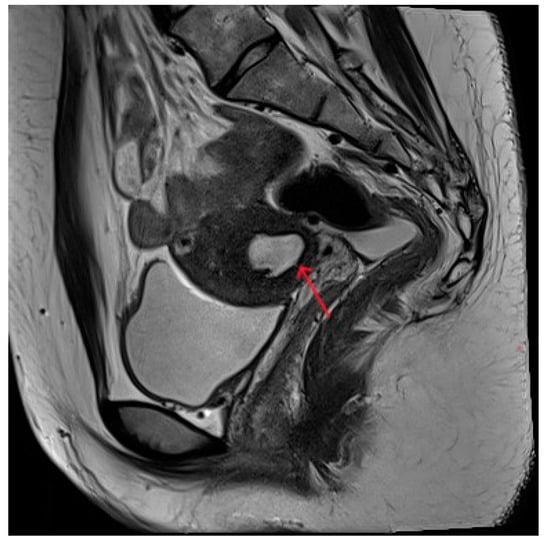

Figure 1.

(a–c) Pelvic MRI: sagittal TIWI sequence (a), sagittal T2WI fat suppression sequence (b), and axial T2WI non-fat suppression (c) showing a cystic lesion in the right posterior wall of the uterus with regular morphology, oval shape, and clear border (red arrows).